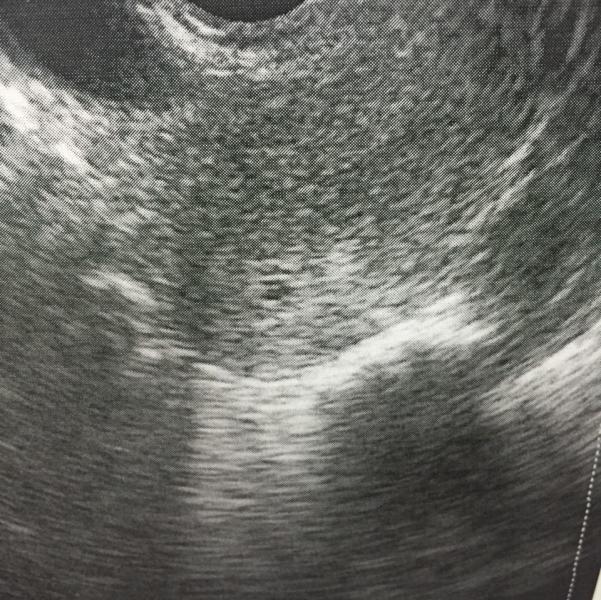

Добрый день всем, мы только вышли с первого УЗИ, были в медцентре компьютерной диагности на толеби Гагарина, там врач высшей категорий узист Аллен Ольга Георгиевна, мы нашли наше маленькое пятнышко, срок 2-3 недели акушерских, и примерно 10 дней реальных, сказала придти через 2 недели, я удивилась что такое маленькое нашли сразу, она еще денег отказалась брать, говорит на повторном буду платить. Вот оно будущее счастье наше. Совсем еще кроха. Она мне очень понравилась. Недавно подруга в двух мес...